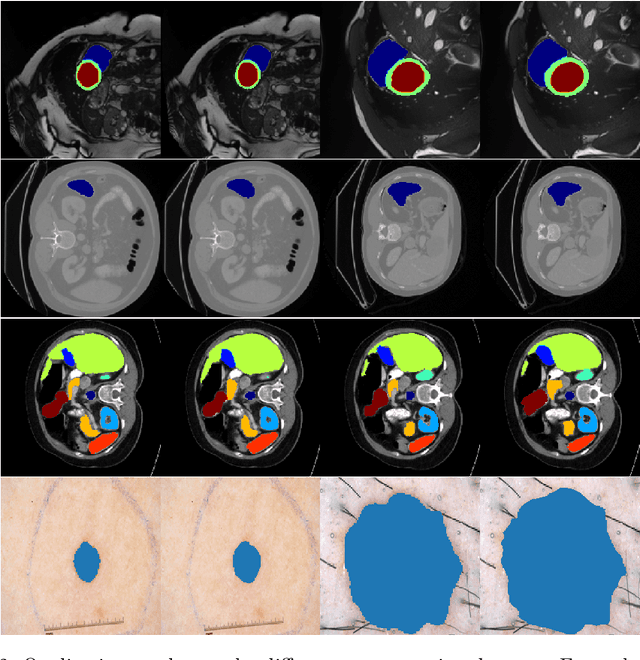

Abstract:We propose a novel transformer-style architecture called Global-Local Filter Network (GLFNet) for medical image segmentation and demonstrate its state-of-the-art performance. We replace the self-attention mechanism with a combination of global-local filter blocks to optimize model efficiency. The global filters extract features from the whole feature map whereas the local filters are being adaptively created as 4x4 patches of the same feature map and add restricted scale information. In particular, the feature extraction takes place in the frequency domain rather than the commonly used spatial (image) domain to facilitate faster computations. The fusion of information from both spatial and frequency spaces creates an efficient model with regards to complexity, required data and performance. We test GLFNet on three benchmark datasets achieving state-of-the-art performance on all of them while being almost twice as efficient in terms of GFLOP operations.

Abstract:The adaptation of transformers to computer vision is not straightforward because the modelling of image contextual information results in quadratic computational complexity with relation to the input features. Most of existing methods require extensive pre-training on massive datasets such as ImageNet and therefore their application to fields such as healthcare is less effective. CNNs are the dominant architecture in computer vision tasks because convolutional filters can effectively model local dependencies and reduce drastically the parameters required. However, convolutional filters cannot handle more complex interactions, which are beyond a small neighbour of pixels. Furthermore, their weights are fixed after training and thus they do not take into consideration changes in the visual input. Inspired by recent work on hybrid visual transformers with convolutions and hierarchical transformers, we propose Convolutional Swin-Unet (CS-Unet) transformer blocks and optimise their settings with relation to patch embedding, projection, the feed-forward network, up sampling and skip connections. CS-Unet can be trained from scratch and inherits the superiority of convolutions in each feature process phase. It helps to encode precise spatial information and produce hierarchical representations that contribute to object concepts at various scales. Experiments show that CS-Unet without pre-training surpasses other state-of-the-art counterparts by large margins on two medical CT and MRI datasets with fewer parameters. In addition, two domain-adaptation experiments on optic disc and polyp image segmentation further prove that our method is highly generalizable and effectively bridges the domain gap between images from different sources.

Abstract:We propose a novel transformer model, capable of segmenting medical images of varying modalities. Challenges posed by the fine grained nature of medical image analysis mean that the adaptation of the transformer for their analysis is still at nascent stages. The overwhelming success of the UNet lay in its ability to appreciate the fine-grained nature of the segmentation task, an ability which existing transformer based models do not currently posses. To address this shortcoming, we propose The Fully Convolutional Transformer (FCT), which builds on the proven ability of Convolutional Neural Networks to learn effective image representations, and combines them with the ability of Transformers to effectively capture long-term dependencies in its inputs. The FCT is the first fully convolutional Transformer model in medical imaging literature. It processes its input in two stages, where first, it learns to extract long range semantic dependencies from the input image, and then learns to capture hierarchical global attributes from the features. FCT is compact, accurate and robust. Our results show that it outperforms all existing transformer architectures by large margins across multiple medical image segmentation datasets of varying data modalities without the need for any pre-training. FCT outperforms its immediate competitor on the ACDC dataset by 1.3%, on the Synapse dataset by 4.4%, on the Spleen dataset by 1.2% and on ISIC 2017 dataset by 1.1% on the dice metric, with up to five times fewer parameters. Our code, environments and models will be available via GitHub.